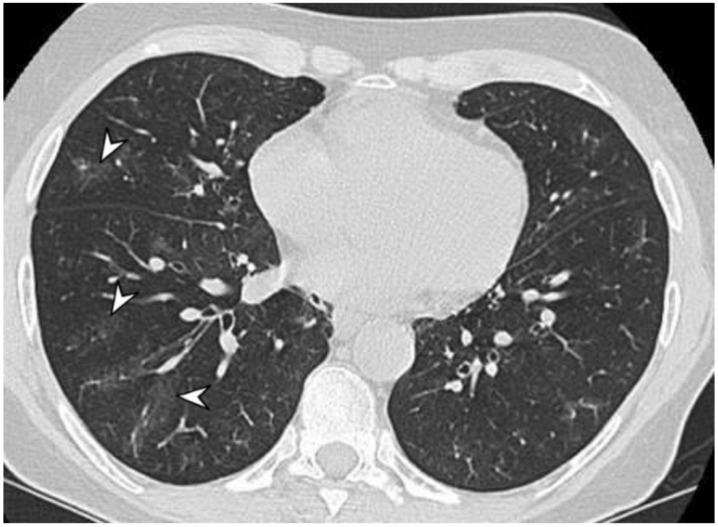

Vasculitides represent a heterogeneous group of immune-mediated disorders, characterized by a systemic inflammatory destructive process of the blood vessels resulting either in ischemia or hemorrhage. The organ involved and vessel size influence the pattern of presentation of the pathology. The lung is commonly involved in systemic vasculitides, with heterogeneous clinical, radiological, and histopathological presentations. Primary vasculitides most commonly associated with lung parenchymal involvement include small-vessel antineutrophil cytoplasmic autoantibody (ANCA)-associated vasculitides, such as granulomatosis with polyangiitis (GPA), eosinophilic granulomatosis with polyangiitis (EGPA), and microscopic polyangiitis (MPA). Several studies have reported cases of interstitial lung diseases (ILDs) associated with systemic vasculitis, particularly those positive for ANCA associated vasculitis/vasculitidis: AAV. We have selected from our case series different radiological features of pulmonary vasculitis (i.e., solitary or multiple nodules, cavitary lesions, nodules with centrilobular or peribronchial distribution, airspace consolidations, "crazy paving" appearance, interstitial disease), including cases with interstitial lung alterations. Therefore, the aim of this review is to describe the typical clinical manifestations of vasculitides and their main radiologic features (especially AAV).

血管炎是一组异质性的免疫介导性疾病,其特征是血管的系统性炎症性破坏过程,可导致缺血或出血。受累器官和血管大小会影响病理表现形式。肺部在系统性血管炎中常受累,临床表现、影像学表现和组织病理学表现各异。最常与肺实质受累相关的原发性血管炎包括小血管抗中性粒细胞胞浆自身抗体(ANCA)相关血管炎,如肉芽肿性多血管炎(GPA)、嗜酸性肉芽肿性多血管炎(EGPA)和显微镜下多血管炎(MPA)。多项研究报告了与系统性血管炎相关的间质性肺疾病(ILD)病例,尤其是那些ANCA相关血管炎/血管炎阳性的病例:AAV。我们从病例系列中选取了肺血管炎的不同放射学特征(即孤立或多发结节、空洞性病变、具有小叶中心或支气管周围分布的结节、气腔实变、“铺路石样”表现、间质性疾病),包括伴有间质性肺改变的病例。因此,本综述的目的是描述血管炎的典型临床表现及其主要放射学特征(尤其是AAV)。